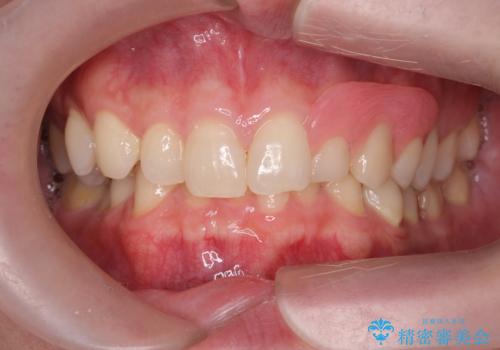

型取りと装着の2回で治療を終了することができました。